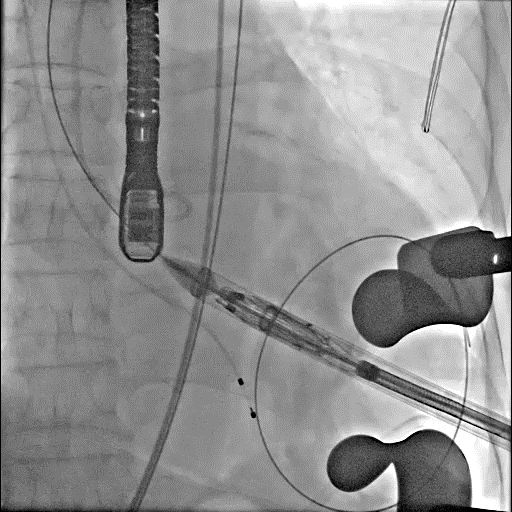

进输送器

定位键入窦

瓣膜释放

术后造影